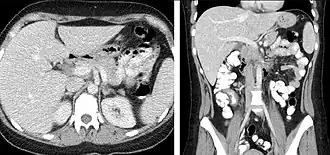

Portal venous phase

The most common technique is to perform portal venous phase imaging in the abdomen and pelvis (approximately 60–90 seconds after contrast administration, figure 2). This results in near optimal contrast opacification of the majority of the solid abdominal organs and it is used for a wide variety of indications: nonspecific abdominal pain; hernia; infection; masses (with a few exceptions such as hypervascular, renal, and some hepatic tumors); and in most follow-up examinations. As a general rule, this single phase is adequate unless there is a specific clinical indication that has been shown to benefit from other phases.

FIGURE 2. Contrast enhanced CT demonstrating parenchymal enhancement of the intra-abdominal organs in the portal venous phase (axial left, coronal reformat right).